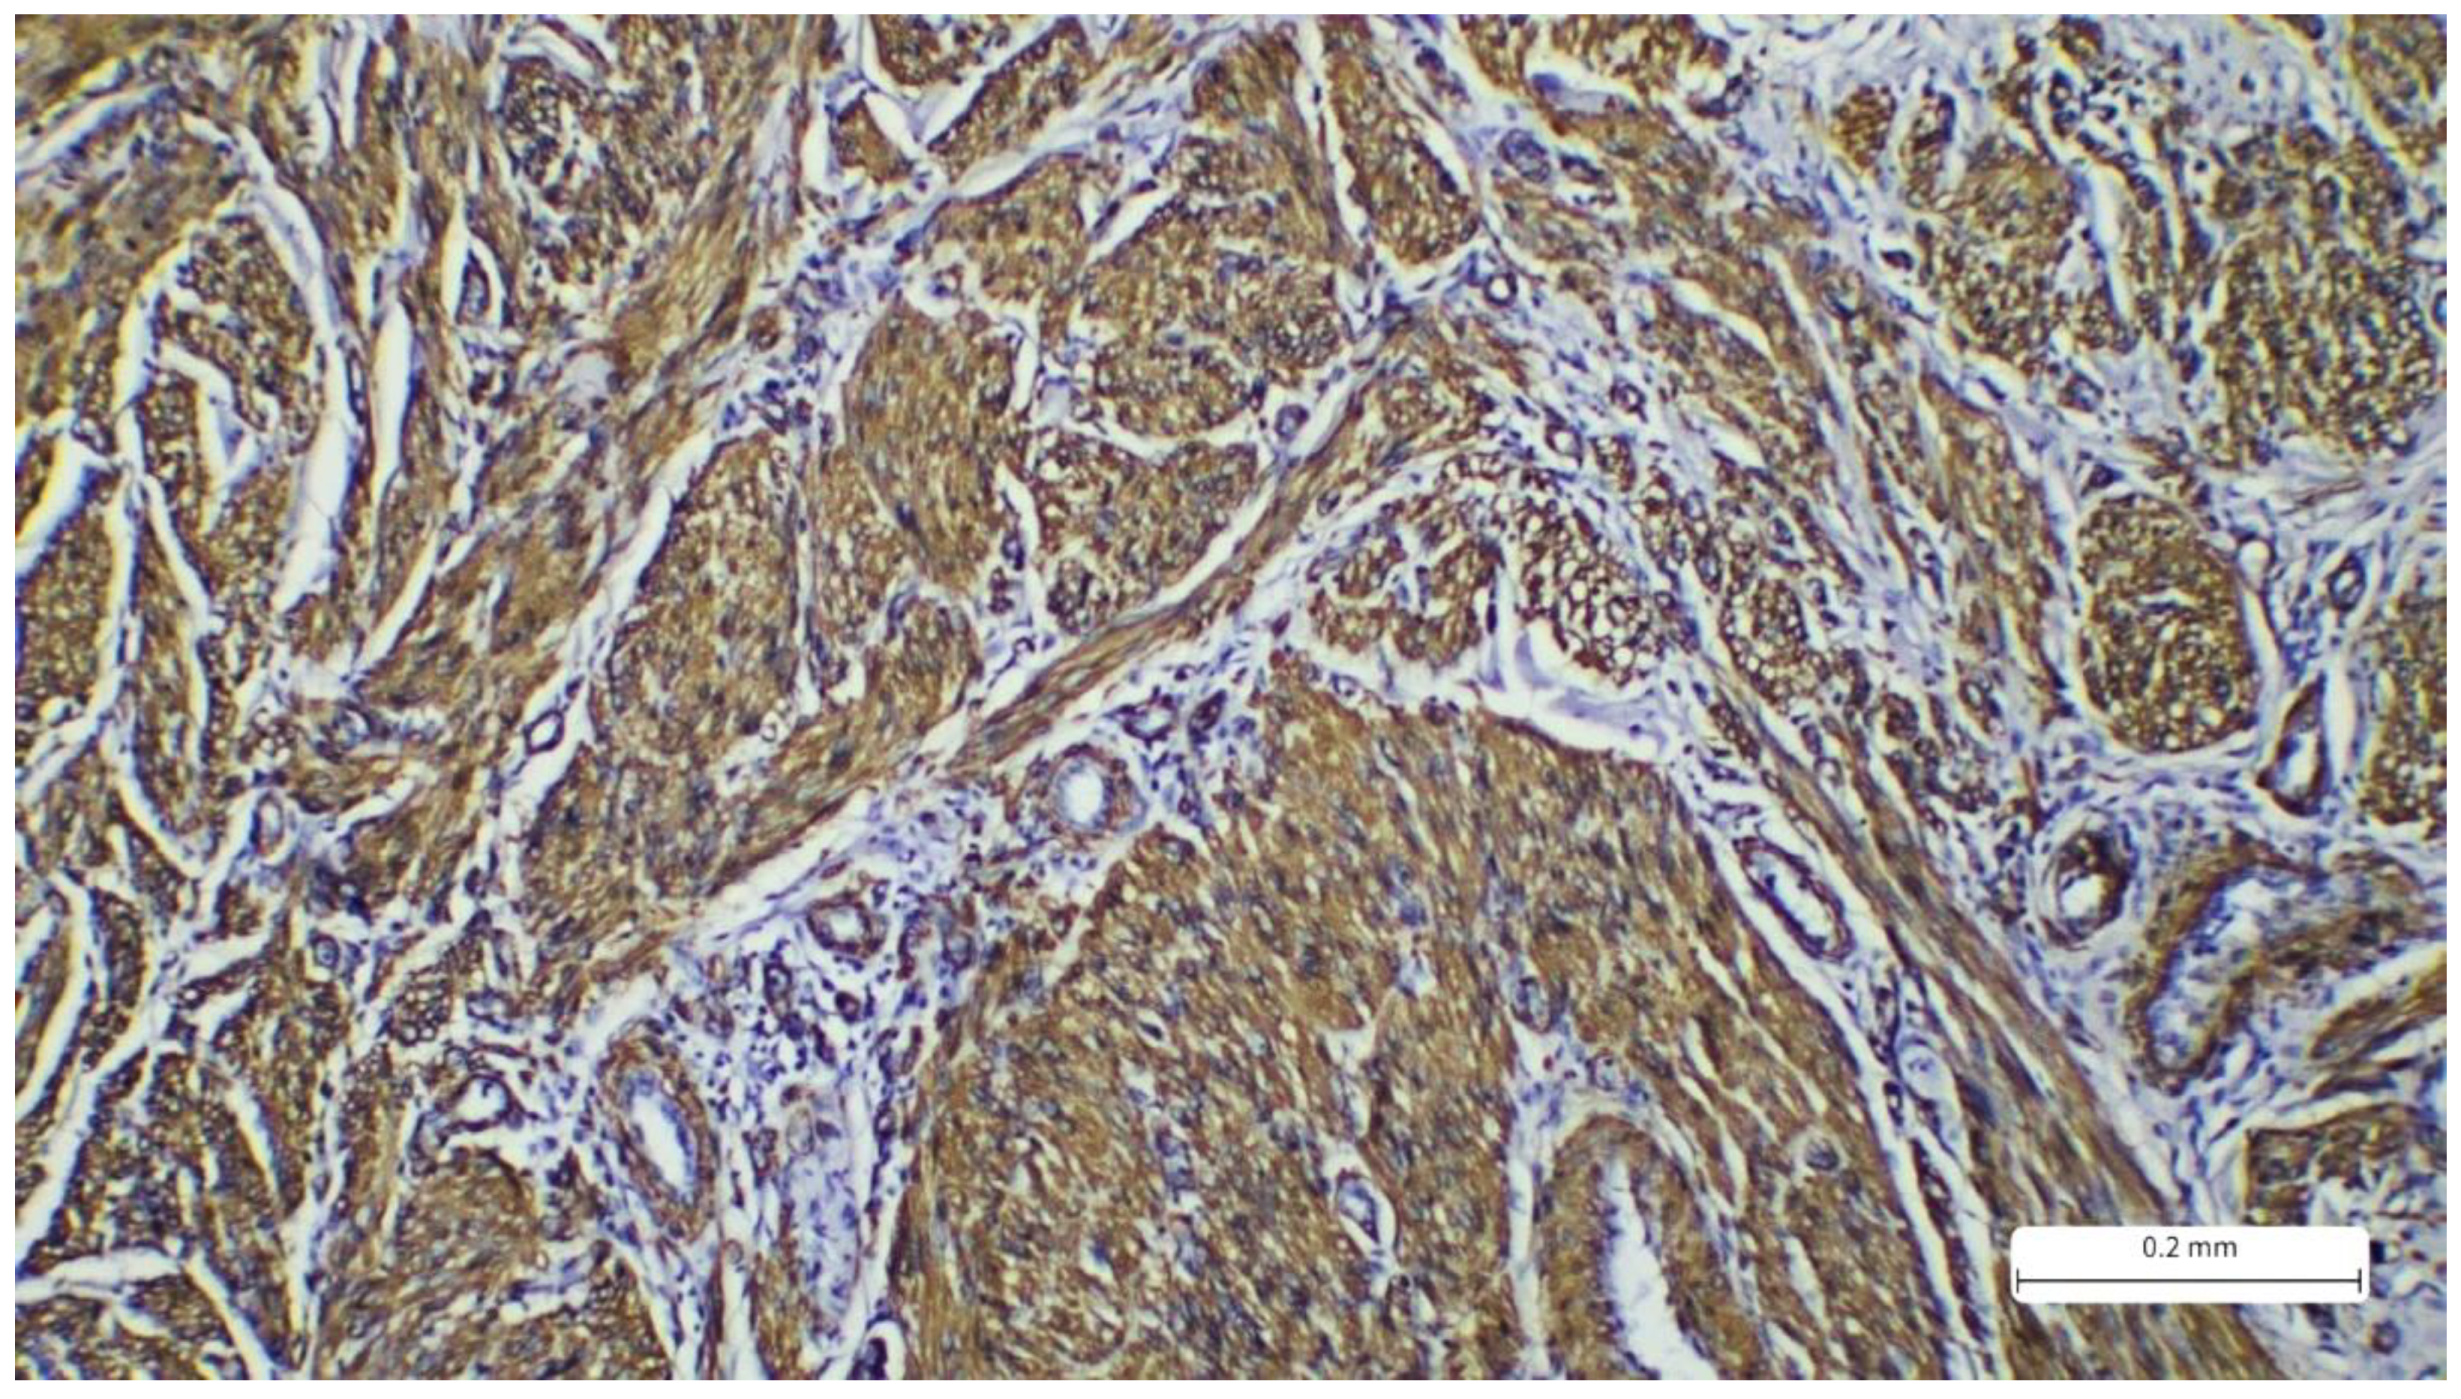

Recurrent Cutaneous Leiomyosarcoma: A Histopathological Perspective and the Quest for Complete Excision

2. Case Report